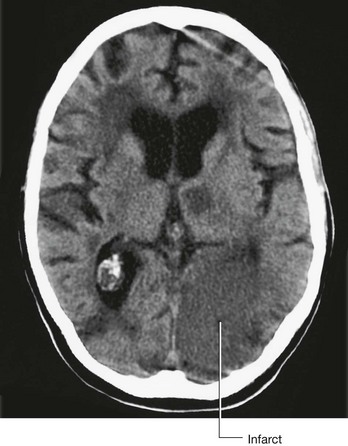

Computed tomography

Since the development of the first computed tomography (CT) scanner, cerebral CT has been the “workhorse” of neuroradiological examination. It is ideally used for head injury because the brain and its coverings can be easily and quickly examined and blood is easily detected. By altering the mathematical algorithm of the data set the bones can also be demonstrated.

With intravenous contrast, CT angiography can be used to demonstrate the position and the size of an intracerebral aneurysm before endovascular treatment.